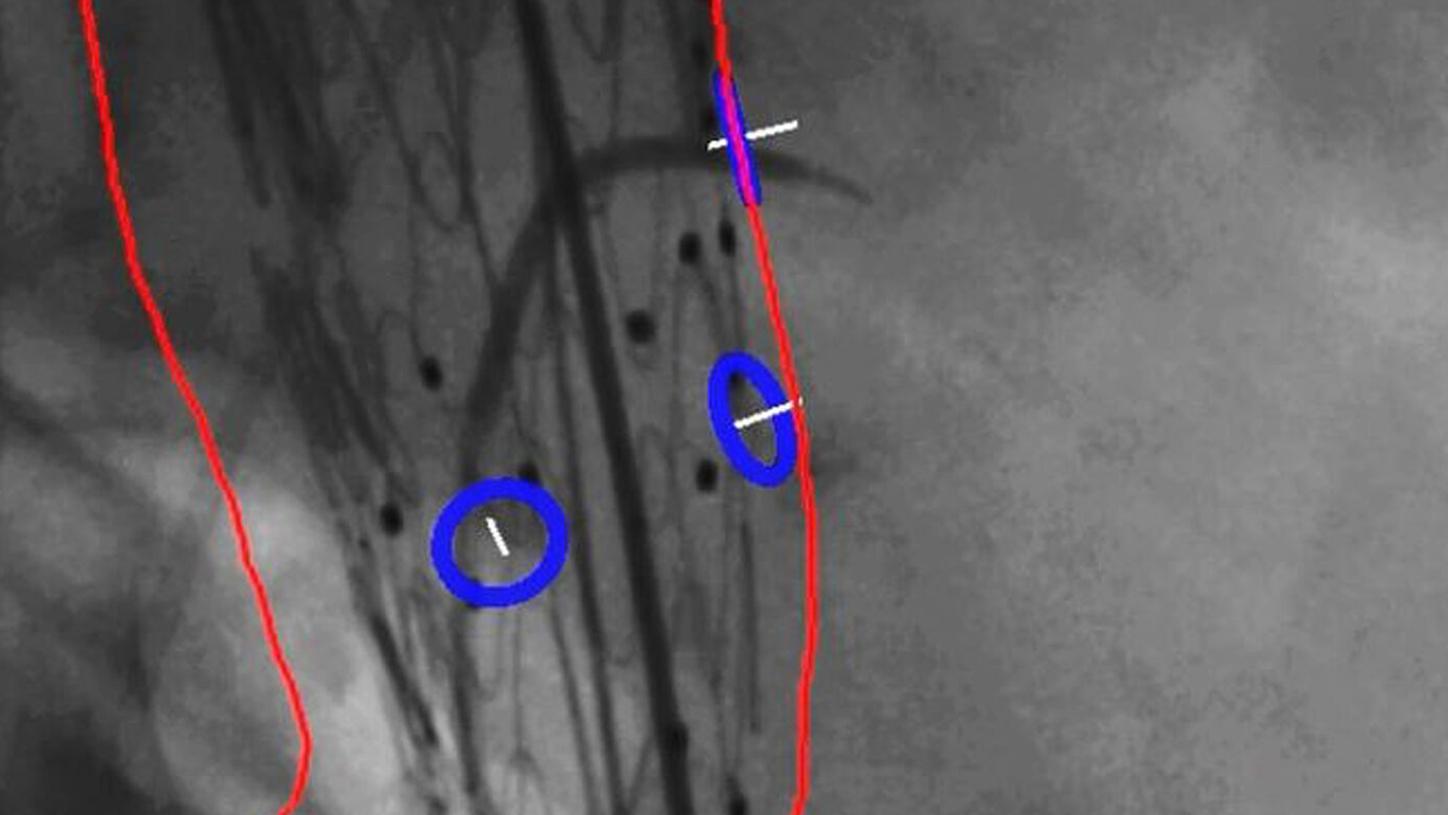

Precise system movements

Precision is key to improve the workflow in complex procedures. The reuse of vessel maps for DSA and 3D Roadmap even after C-arm and table movements speeds up the intervention and reduces dose and use of contrast media. ARTIS icono supports this with a (re)positioning accuracy of better than 0.5 mm.